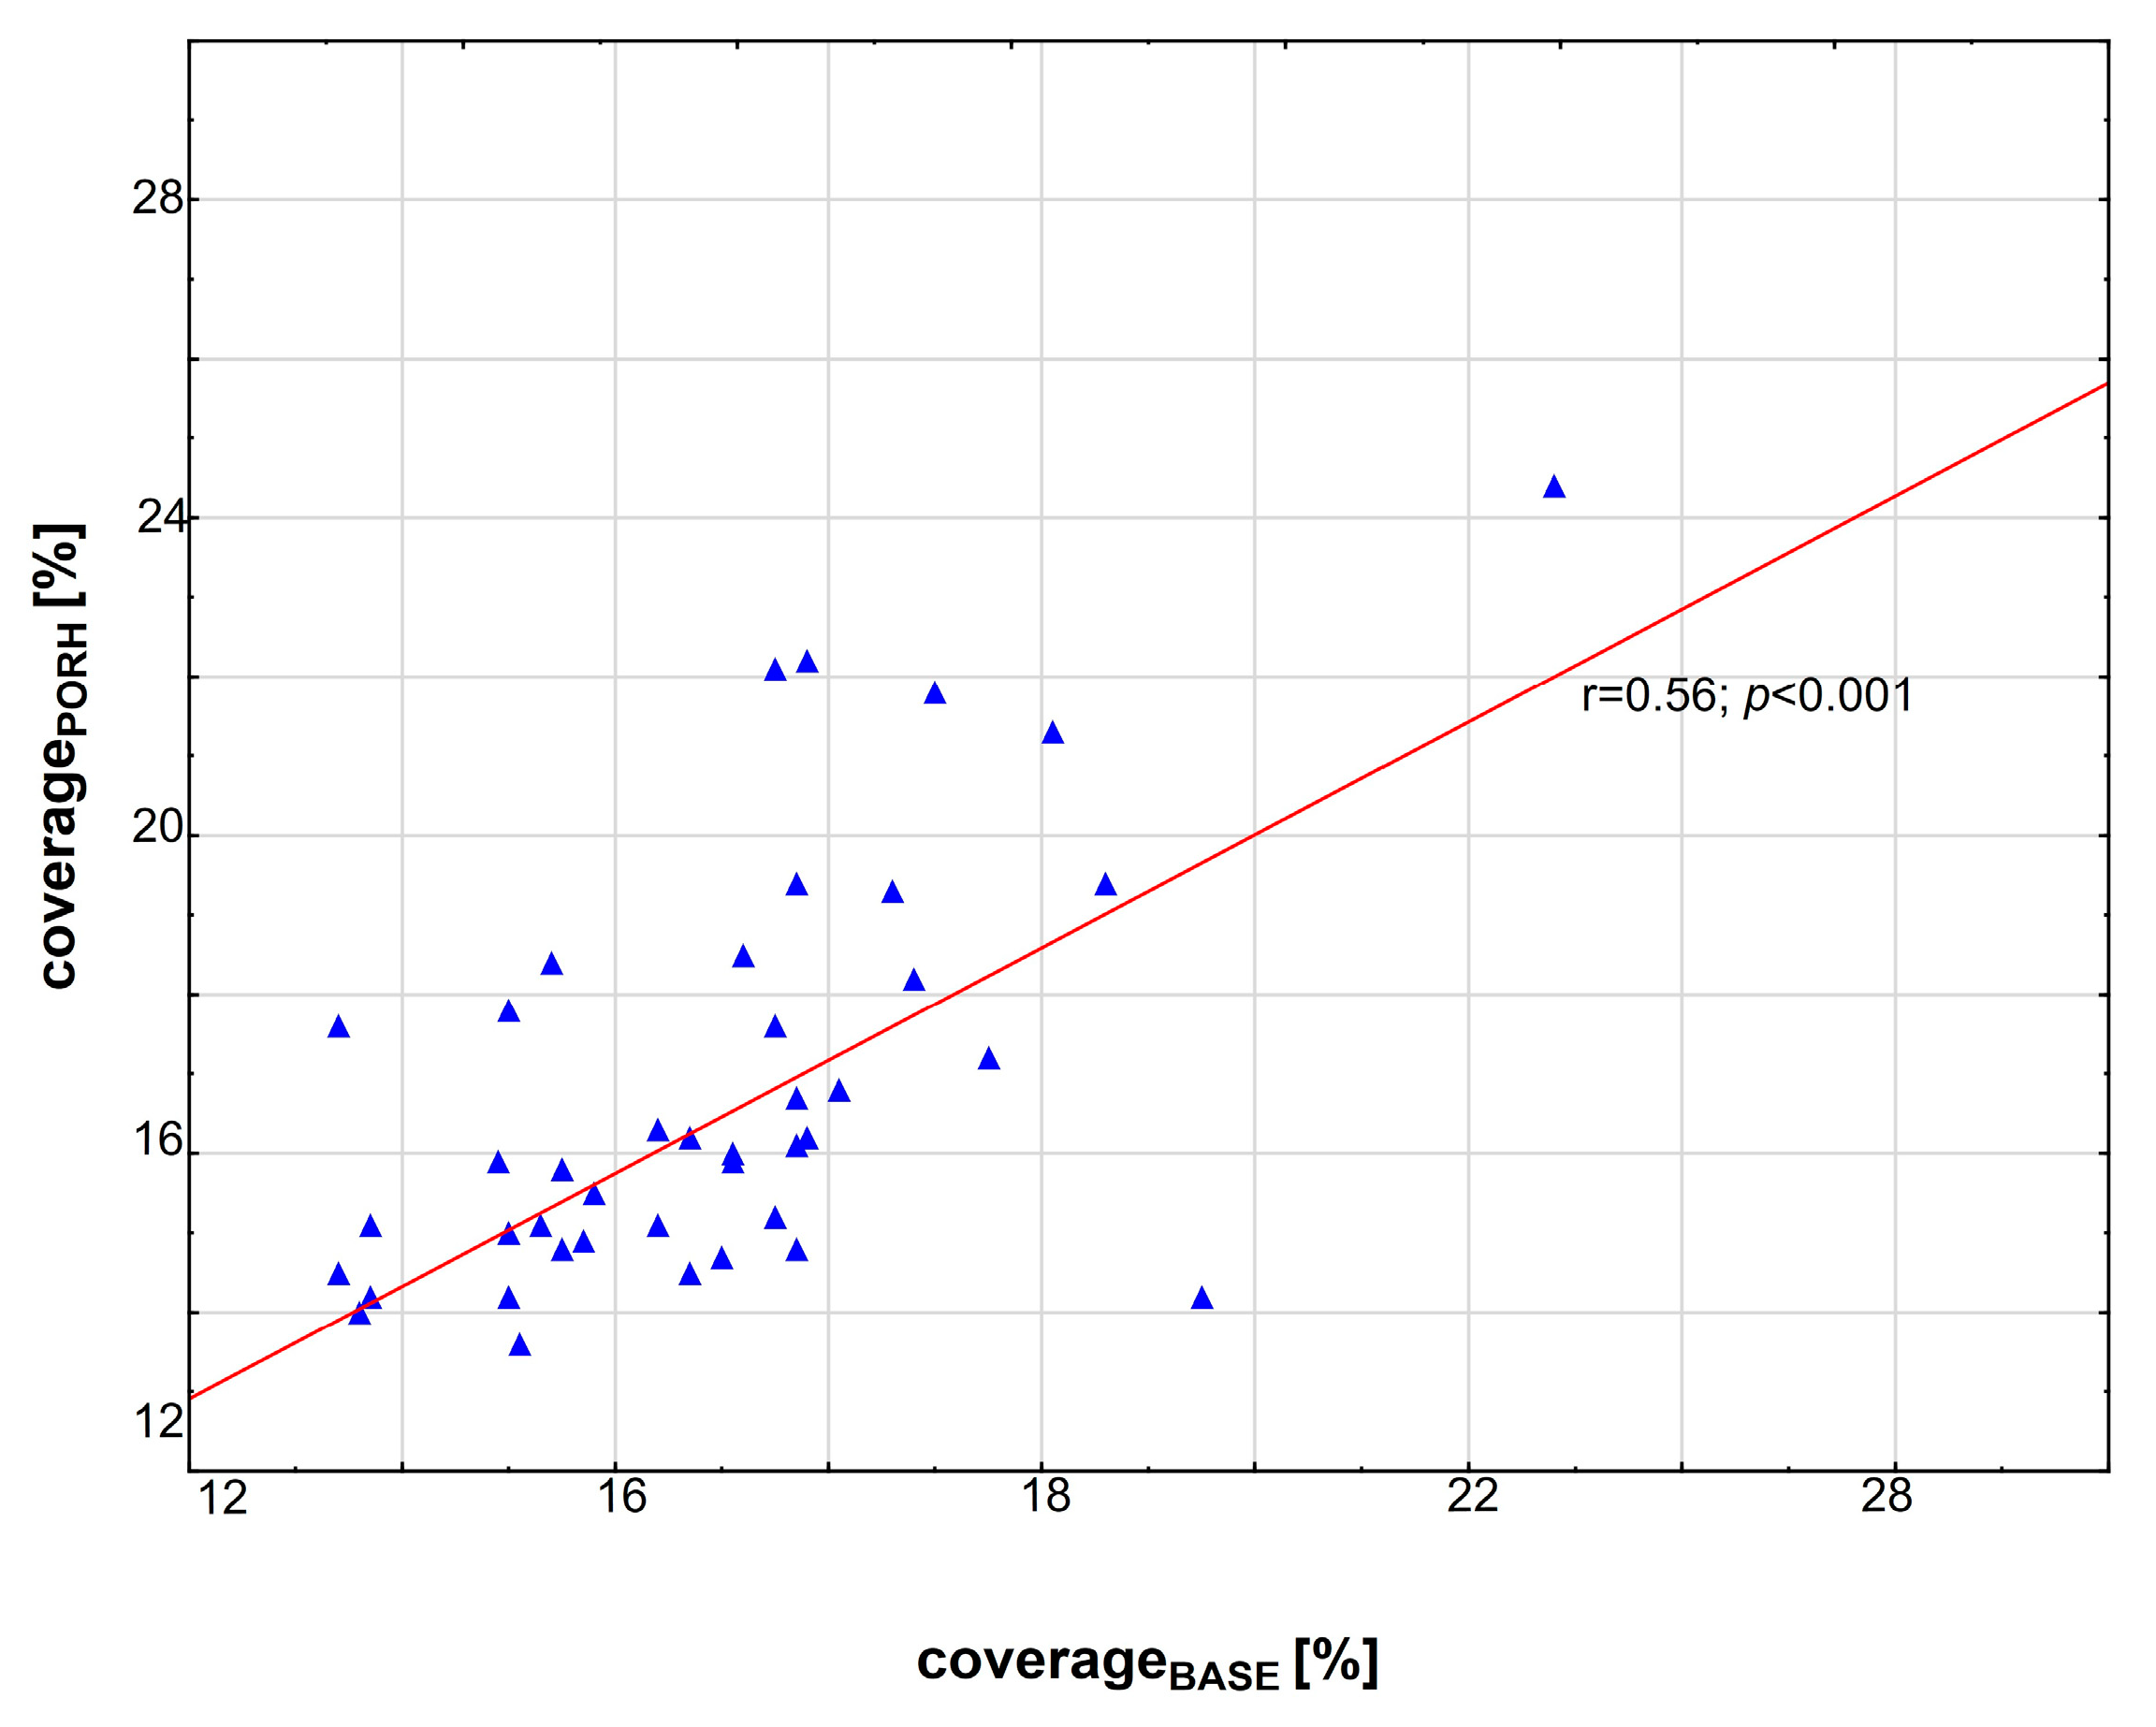

3.2. Correlations between Variables

| coverage before PORH test [ %] (coverageBASE) | ||||

| baseline | 17.1 (12.7–24.8) | 15.4 (12.7–17) | 17.8 (17.1–24.8) | --- |

| after one year | 18 (12–23) | 17(12–22) | 18 (15–23) | 0.33 |

| p for one year comparison | 0.19 | 0.03 | 0.54 | |

| coverage after PORH test [%] (coveragePORH) | ||||

| baseline | 16 (10.4–24.4) | 15 (10.4–18.4) | 17.2 (11.5–24.4) | <0.001 |

| after one year | 16 (11–24) | 17 (11–24) | 16 (11–20) | 0.56 |

| p for one year comparison | 0.88 | 0.07 | 0.02 | |